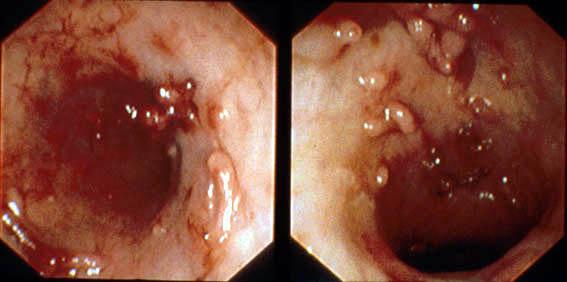

A case of ulcerative colitis showing a progression and remission of diffuse inflammatory polyposis during over a ten-year period.

Tokyo Pref., Cooperative study between National Cancer Center and Kyushu Cancer Center

Inflammatory or ulcerative disease / lesions/Ulcerative colitis

Large intestine(Colon)/Descending colon

Endoscopy